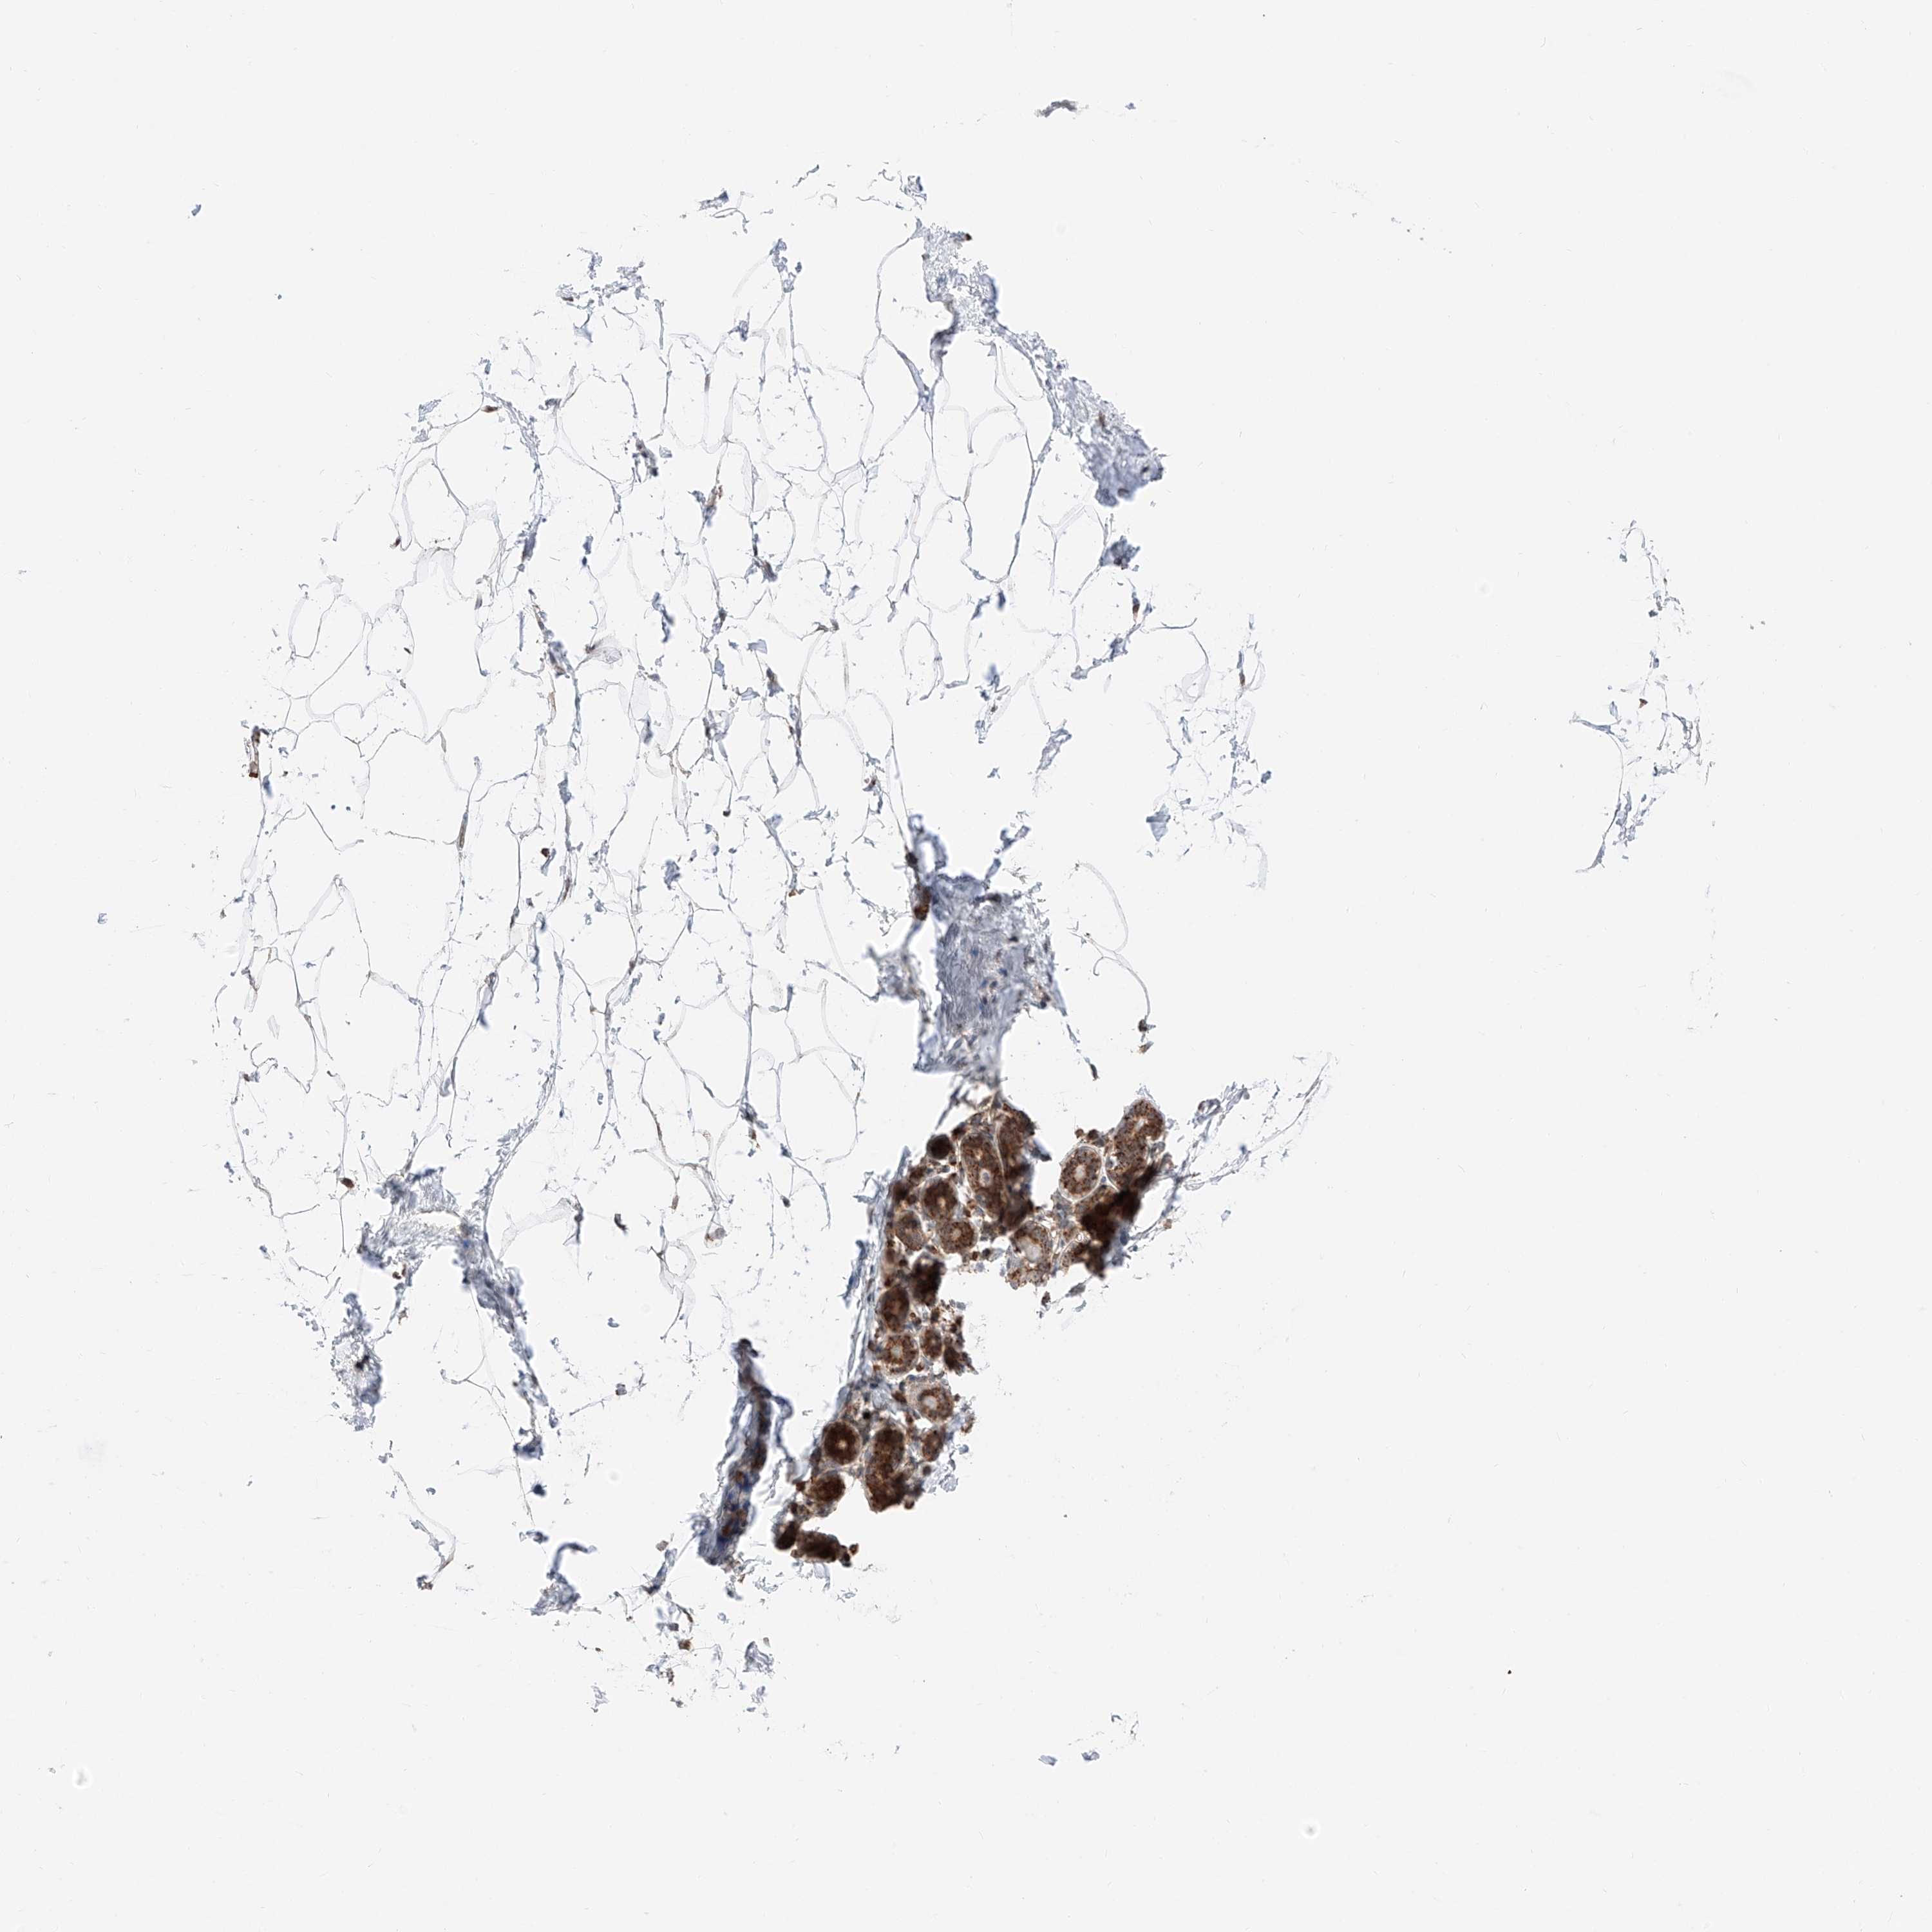

BREAST - Antibody stainingi

Antibody staining in the annotated cell types in the current human tissue is reported as not detected, low, medium, or high, based on conventional immunohistochemistry profiling in selected tissues. This score is based on the combination of the staining intensity and fraction of stained cells.

Each image is clickable and will lead to virtual microscopy that enables deeper exploration of all samples and also displays staining intensity scores, fraction scores and subcellular localization as well as patient and tissue information for each sample.

Antibody HPA007241Antibody HPA011109

Adipocytes MediumNot detected

Glandular cells HighHigh

Myoepithelial cells HighMedium